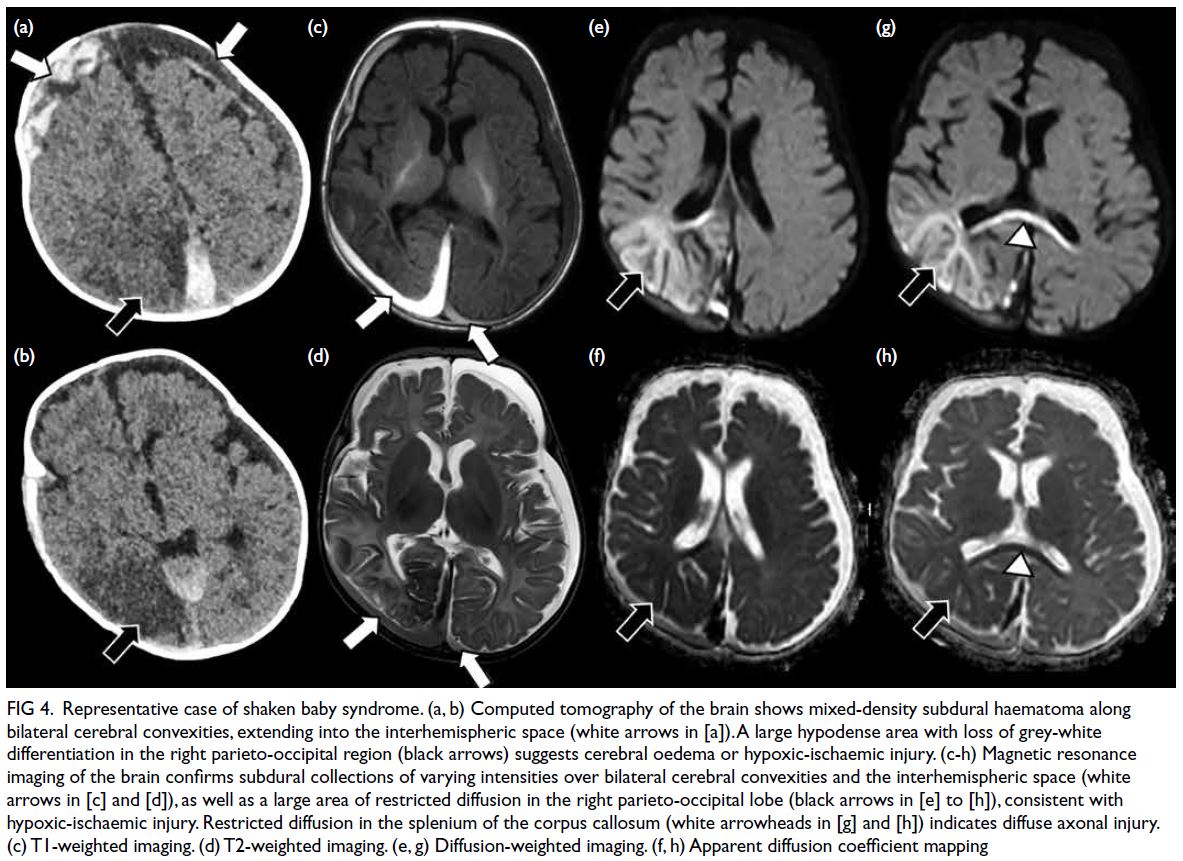

Computed tomography (CT) was the

initial imaging modality in 24 cases evaluated for

suspected intracranial injury; five cases (20.8%)

showed positive findings. Three cases (12.5%)

demonstrated alarming features suggestive of shaken

baby syndrome on initial brain CT scans, including

subdural haemorrhage (n=3) and cerebral oedema

(n=1), prompting further evaluation by MRI. Shaken

baby syndrome was confirmed in all three cases on

MRI, which showed subdural haemorrhage (n=3)

and brain parenchymal injuries, including diffuse

axonal injury (n=3) and hypoxic-ischaemic injury

(n=2) [Fig 4]. These patients, aged between 2 and

7 months, presented with non-specific symptoms

such as seizures (n=3), vomiting (n=2), and loss of

consciousness (n=1). Fundoscopic examination

confirmed multilayered retinal haemorrhages in all three cases, whereas skeletal surveys were

unremarkable (Table 2). The remaining two CT-positive

cases included one with a scalp haematoma

and another with a mildly depressed parietal skull

fracture; both lacked intracranial findings.

Figure 4. Representative case of shaken baby syndrome. (a, b) Computed tomography of the brain shows mixed-density subdural haematoma along bilateral cerebral convexities, extending into the interhemispheric space (white arrows in [a]). A large hypodense area with loss of grey-white differentiation in the right parieto-occipital region (black arrows) suggests cerebral oedema or hypoxic-ischaemic injury. (c-h) Magnetic resonance imaging of the brain confirms subdural collections of varying intensities over bilateral cerebral convexities and the interhemispheric space (white arrows in [c] and [d]), as well as a large area of restricted diffusion in the right parieto-occipital lobe (black arrows in [e] to [h]), consistent with hypoxic-ischaemic injury. Restricted diffusion in the splenium of the corpus callosum (white arrowheads in [g] and [h]) indicates diffuse axonal injury. (c) T1-weighted imaging. (d) T2-weighted imaging. (e, g) Diffusion-weighted imaging. (f, h) Apparent diffusion coefficient mapping